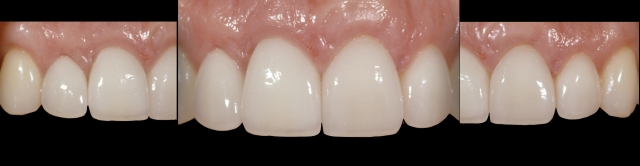

The following female patient lost her right central due to trauma and was treated at the age of 24 with a single tooth implant in the #8 site and veneers on teeth #’s 7, 9, 10 (See Fig.1). The definitive result shows nice symmetry in both the incisal edge positions and gingival margins of the central incisors (See Fig.2). At the 6-year follow up, a discrepancy can be seen in the incisal edge positions of the centrals (See Fig 3) The incisal edge discrepancy is significantly greater at 12 years (See Fig. 4). To what can we attribute this change? Is it due to eruption of the anterior teeth due to unstable occlusal contacts? Or is it due to eruption of the teeth due to continued facial growth?